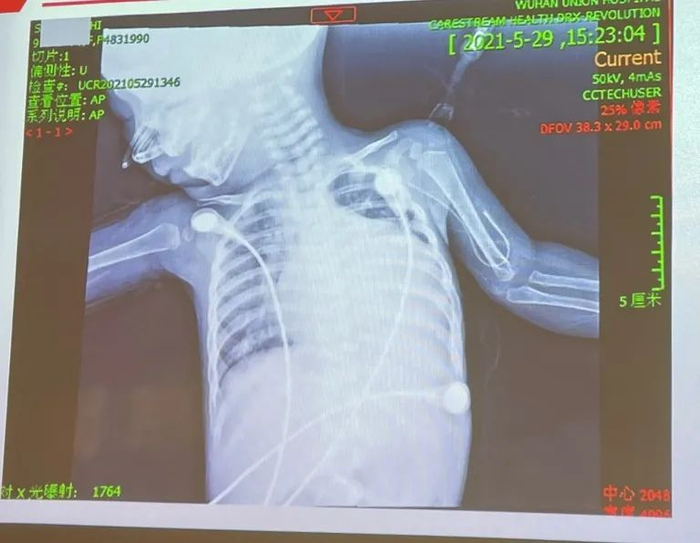

后续检查发现涵涵心脏扩大压迫左肺